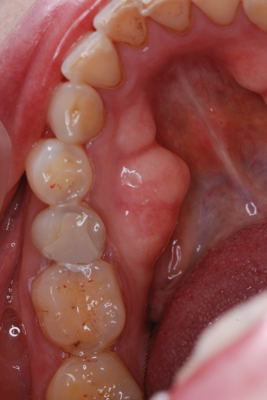

| 今回の写真は下顎隆起です。下顎骨の内側が写真の様に出っ張っています。症状はありません。これは、歯でも根でも無く骨なのです。腫瘍ではないかと心配して相談に来る方もいらっしゃいます。しかしただの骨の出っ張りで腫瘍などの悪い病気ではありません。原因は不明ですが小さい物を含めると結構な頻度で出現します。下顎の場合はこの場所で、上顎の場合は真ん中(口蓋中央部)に多いです。 | ![]() ![]() |

| この骨隆起も大きいです。個数、形がほぼ左右対称に出現するのが不思議です。 | ![]() |